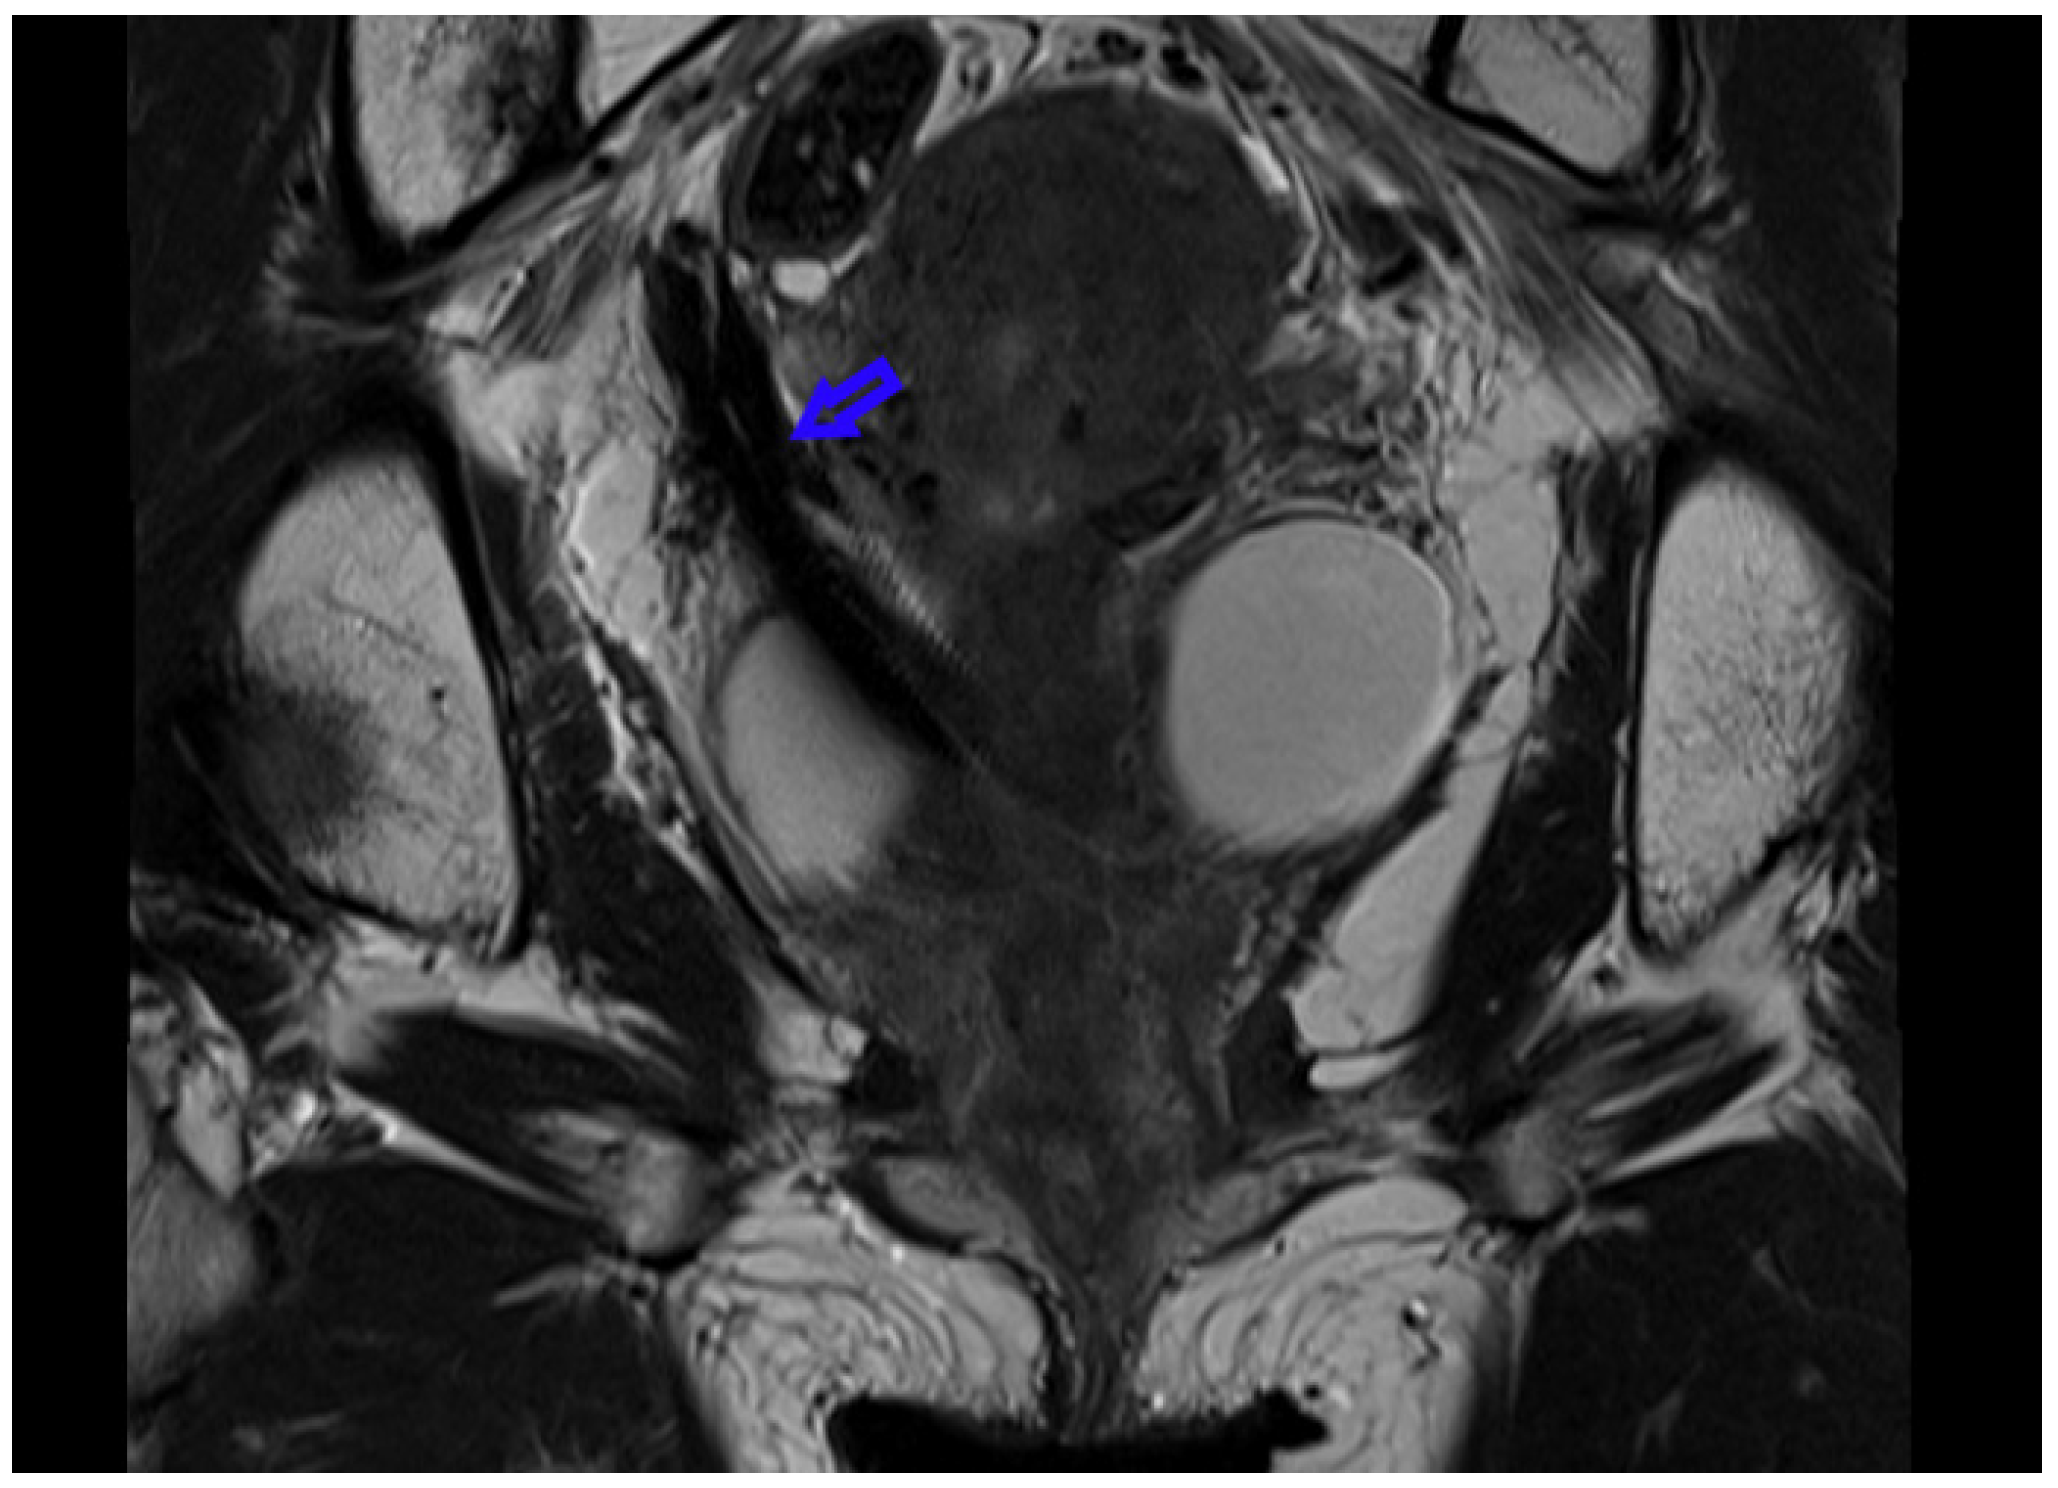

While ureteral stents produce markedly less artefact than larger metallic implants (such as joint prostheses), their location (particularly where MRI of the pelvis is concerned) can have impact on diagnosis and staging. In MRI of pelvic cancer, the posterior relation of the stented ureter may impact the diagnostic imaging produced[5] (Figure 1).

Figure 1.

Gross stent-related artefact on coronal MRI of patient with Teleflex Rüsch DD Tumour Stent in situ.

The Figures (using the Teleflex Rüsch DD Tumour Stent) highlight the potential for metallic stents to produce clinically significant artefact. The patient is a 39-year-old woman with metastatic squamous cell carcinoma of the cervix, with locally advanced pelvic disease, and retroperitoneal metastasis. She presented with malignant right ureteric obstruction and urosepsis. The ureteric stent was inserted to improve drainage while on chemotherapy, and management of malignant obstructive uropathy.

In patients such as the above, the role of MRI is multi- faceted, in that it is used for treatment planning, local staging, and for consideration of radical salvage surgery (for example, anterior or total pelvic exenteration, which is offered at this centre). As seen on this re-staging study, the artefact produced by the stainless steel cross- braiding component of the stent markedly compromises image quality, and with it, diagnostic certainty. A similar effect is not seen in CT imaging (Figure 2).